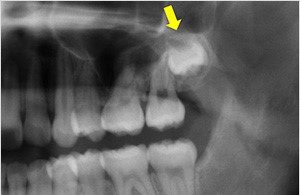

2.歯並びに悪影響が出ている、もしくは手前の歯を溶かしている

親知らずは横向きに生えることが多いです。 横向きに生えた親知らずは手前の歯をグイグイと押し、歯並びに悪影響を与えることがあります。

また、横向きに生えた親知らずが手前の歯を押し、根っこが溶かされてしまうことがあります。